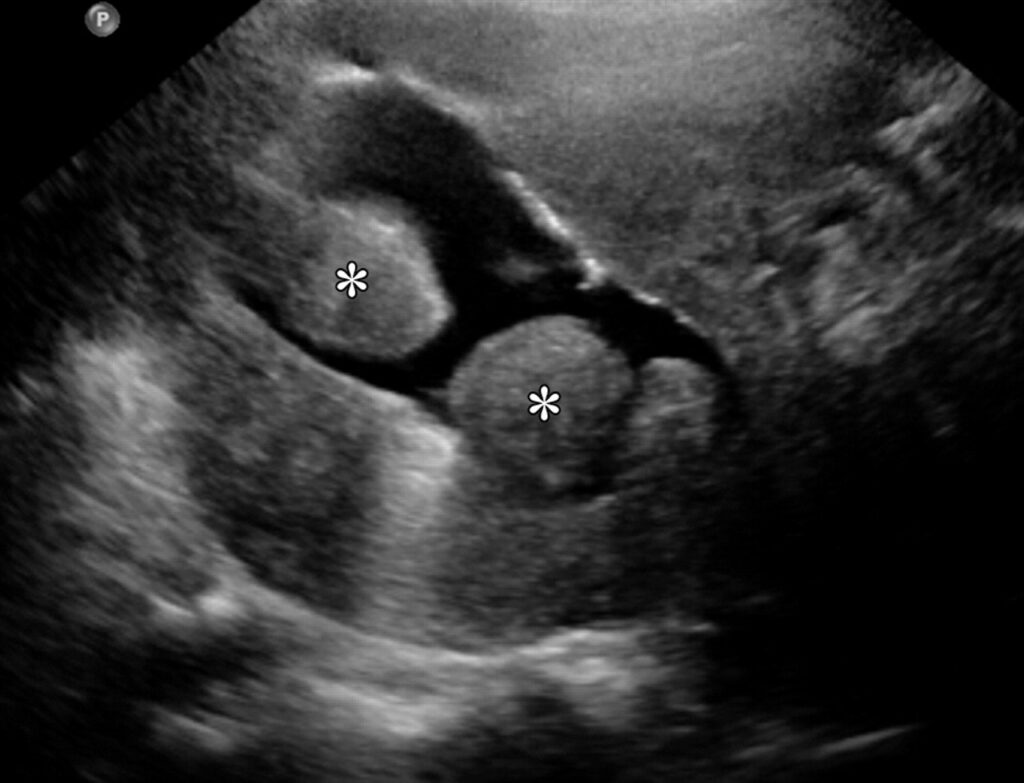

– Về chẩn đoán hình ảnh, cần chẩn đoán phân biệt UXCTC và bệnh tuyến cơ tử cung (Xem ảnh):

A: phân bố mạch máu quanh UXCTC trên siêu âm doppler

B: UXCTC trên siêu âm thang xám ngả âm đạo

C: bệnh tuyến cơ tử cung (adenomyosis) trên siêu âm thang xám ngả âm đạo

D: phân bố mạch đâm xuyên qua tổn thương (mạch lưới) bệnh tuyến cơ tử cung (adenomyosis) trên siêu âm doppler

Siêu âm là phương tiện khảo sát hình ảnh chủ lực trong khảo sát, đánh giá các bệnh lý lành tính của tử cung [4]. Hình ảnh điển hình của u xơ-cơ tử cung trên siêu âm thang xám là ổ hồi âm kém hoặc không đồng nhất, có giảm âm phía sau, giới hạn rõ, phân biệt rõ với mô chung quanh, phân bố mạch máu viền quanh tổn thương trên siêu âm doppler.

– Siêu âm doppler: đánh giá phân bố mạch máu trong UXCTC, chẩn đoán phân biệt dạng phân bố xuyên tổn thương trong bệnh tuyến cơ tử cung (adenomyosis). Ngoài ra, siêu âm doppler đánh giá chỉ số đập (PI) và chỉ số kháng trở (RI) động mạch cũng giúp ích trong chẩn đoán phân biệt UXCTC và bệnh tuyến cơ tử cung.